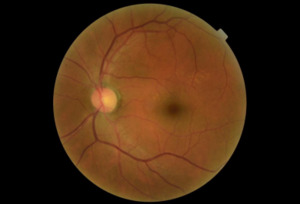

A dilated fundus examination was performed. The retina presented with a variety of diffuse hemorrhages varying from subhyaloid to intraretinal along with cotton wool spots and Rothspots in both eyes. The optic nerve presentation of each eye was normal and well perfused with no signs of abnormalities. At the completion of examination, the patient was diagnosed with an acute severe nongranulomatous anterior uveitis of the right eye and presumed severe non-proliferative diabetic retinopathy of both eyes. One year prior, the patient was seen for a comprehensive eye exam and was diagnosed with only mild nonproliferative diabetic retinopathy, see Images 1-4 for comparison.

Due to the severity of the anterior chamber reaction and the progression of the retinopathy, a full blood panel workup was ordered to determine if the findings were attributed to an infectious, inflammatory, or a neoplastic etiology. Differential diagnoses to consider for an acute nongranulamatous uveitis are conditions associated with human leukocyte antigen B27 (HLA-B27) such as, Reiter syndrome, inflammatory bowel disease including ulcerative colitis and Crohn’s disease, ankylosing spondylitis, Behcet disease and psoriatic arthritis. Other etiologies that can contribute to an acute nongranulomatous uveitis are lyme disease and acute trauma.4 Fundoscopic manifestations with marked hemorrhaging in the presence of Roth spots and cotton wool spots should be suspected for vascular and hematological abnormalities such as diabetes, leukemia, septic chorioretinitis secondary to bacterial endocarditis, anemia and sickle cell disease.4 This patient’s PCP was alerted to the ocular findings and possible concerns. Included in the blood panel orders (Table 1, reference 1 for abbreviations) were: a CBC with differential, ESR, CRP, ANA, ACE, RA, HLA-B27 and FTA-ABS.

Of all leukemia related ocular involvement, retinal involvement or leukemic retinopathy is the most common, occurring in 50-70% of patients.3,6 These posterior segment findings are typically a secondary or indirect manifestation resulting from tributary hematological abnormalities caused by the leukemia.5 Leukemia can cause secondary complications such as anemia, thrombocytopenia, hyperviscosities, etc .2,7 In the retina, these findings usually manifest as retinal vascular changes including intraretinal hemorrhages, cotton wool spots, white-centered hemorrhages or Roth spots, as well as vitreous hemorrhaging or vascular occlusions.3,8,9 The retina is the most involved ocular structure and it is estimated that nearly 70-90 percent of all patients diagnosed with leukemia will show fundus abnormalities at some point during their illness..3 Fundus findings are more prevalent in acute versus chronic leukemias and in myelogenous versus lymphocytic. Therefore, AML is associated with the highest occurrence of retinopathy.3 Abu el-Asrar et al. retrospectively evaluated the prognostic importance of retinopathy in adult and pediatric leukemia patients. They reported that the three-month mortality rate of patents with cotton-wool spots is eight times higher than in patients without these retinal lesions.3,10